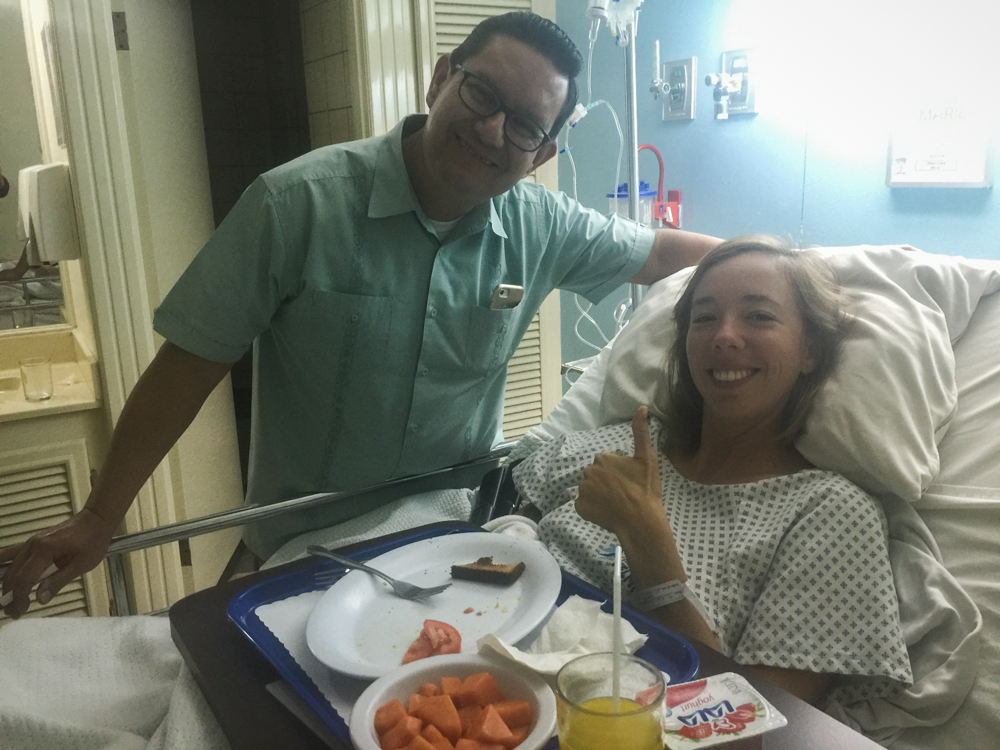

The nurses then fed me breakfast, my first and very highly anticipated meal in 24 hours, and sent Christian down to the front desk to pay the remainder of the bill and got me up and walking to prepare for my exit. It was painful and slow, but amazingly, I felt better than I had in months. My pain relief from my nerve was immediate, and though the surgical site would need time to heal, I was in high spirits.

TOTAL COST OF EVERYTHING: $5240

Dr. Fong, my hero!